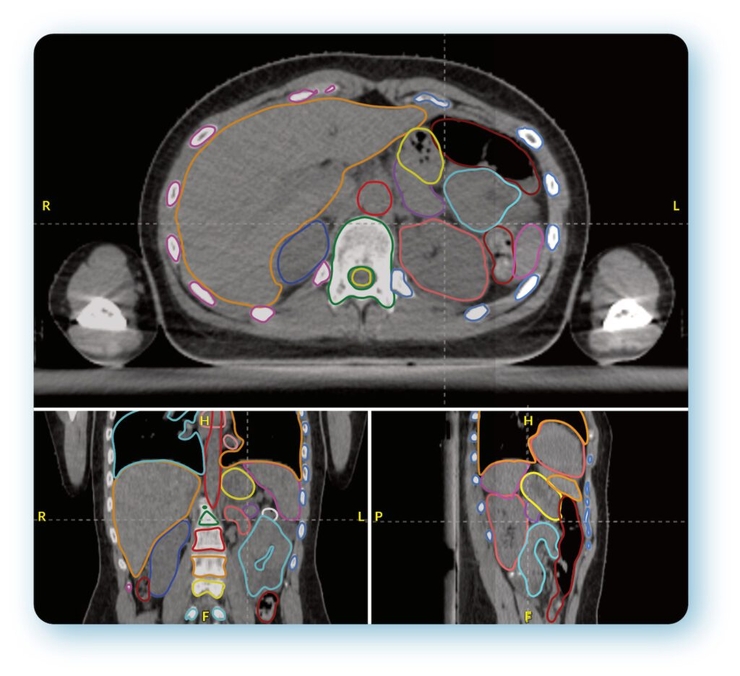

It will initially involve AutoContour, an artificial intelligence-driven solution to speed up the pre-treatment planning process, and cloud-based quality assurance platform RadMachine to ensure the safety and optimal performance of treatment delivery systems, imaging technology, and ancillary equipment.